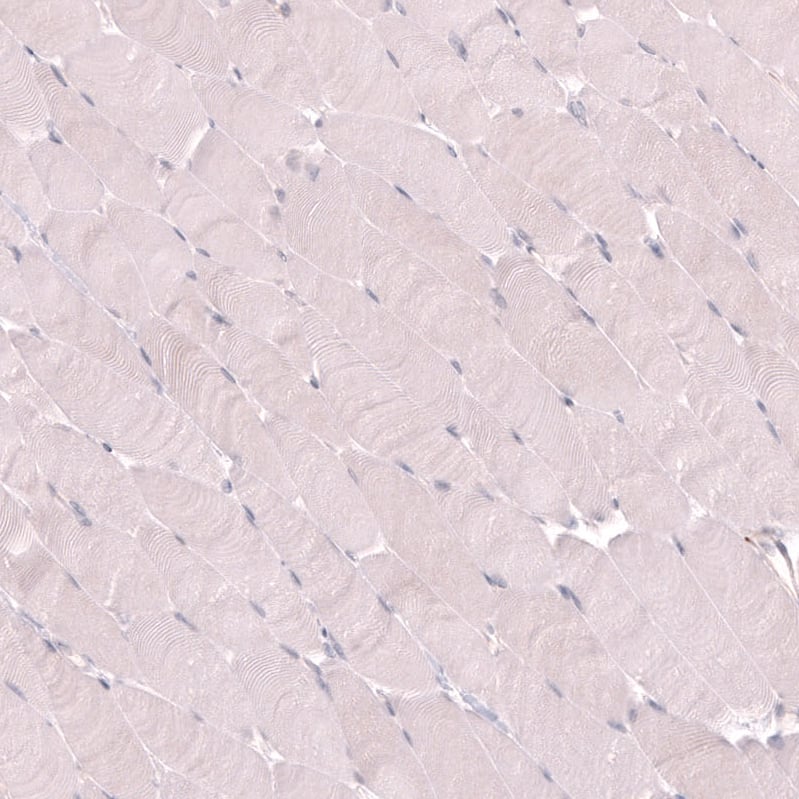

VMAT2 Antibody (CL13157) - Azide and BSA Free Immunohistochemistry-Paraffin: VMAT2 Antibody [NBP3-44388]

Immunohistochemistry-Paraffin: VMAT2 Antibody [NBP3-44388]

Staining of human skeletal muscle shows no positivity in myocytes as expected.